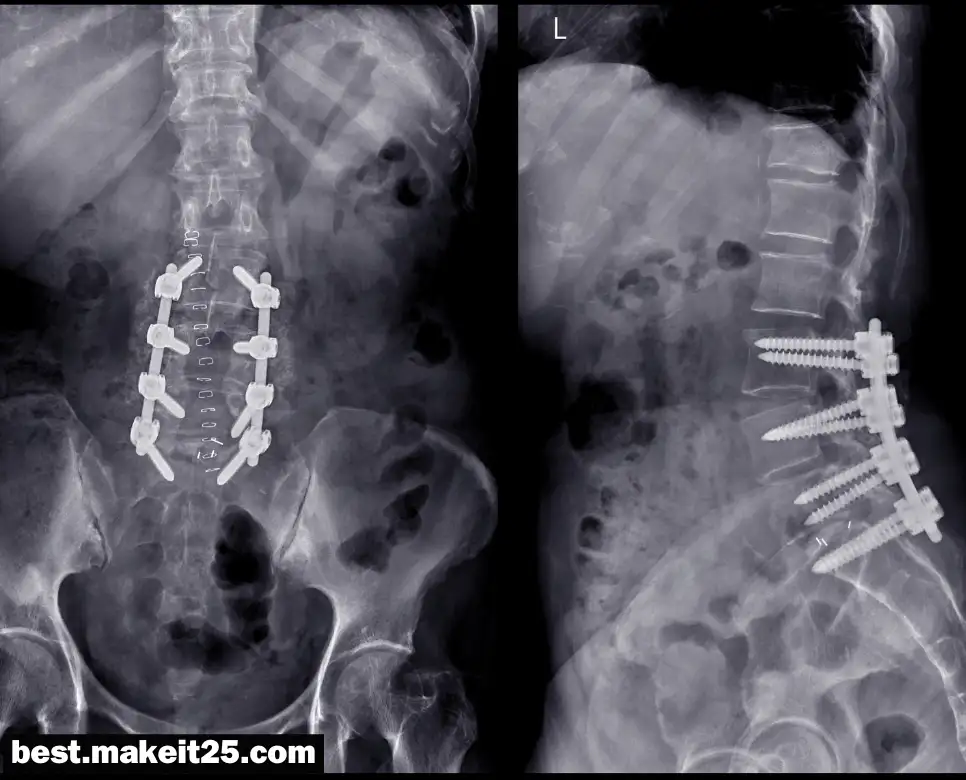

의학 용어 ‘LAT’는 주로 방사선 촬영에서 사용되는 용어로, ‘Lateral’의 약자입니다. 이는 옆면 또는 측면을 의미하며, 특히 X선 촬영에서 환자의 옆면을 찍는 방법을 지칭할 때 사용됩니다. ‘LAT’ 촬영은 특정 부위의 구조와 병변을 더 명확하게 파악하기 위해 필요합니다.

방사선 촬영에서 ‘LAT’는 환자의 측면에서 촬영하는 것을 의미합니다. 이 방법은 특히 척추, 두개골, 사지 등의 영상을 얻기 위해 사용되며, 다음과 같은 경우에 필요합니다:

- 척추의 측면 촬영: 척추의 곡률, 변형, 또는 병변을 평가하기 위해 사용됩니다.

‘LAT’ 촬영은 다양한 진단 및 치료 과정에서 중요한 역할을 합니다. 의사는 LAT 촬영을 통해 얻은 영상을 분석하여 다음과 같은 조치를 취할 수 있습니다:

- 정확한 진단: 영상을 통해 정확한 진단을 내리고 적절한 치료 계획을 세울 수 있습니다.

- 치료 효과 모니터링: 치료 과정 중에 정기적인 LAT 촬영을 통해 치료의 효과를 모니터링할 수 있습니다.

- 수술 계획: 수술 전 LAT 촬영을 통해 수술 계획을 세우고 수술 중에도 영상을 참고할 수 있습니다.